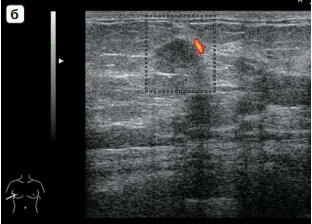

Инфильтративный Рак Молочной Железы Фото